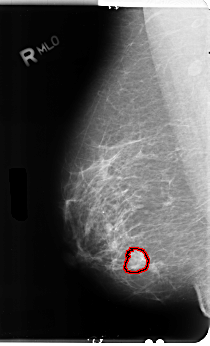

B_3106_1.RIGHT_MLO

RIGHT_CC LINES 4712 PIXELS_PER_LINE 2800 BITS_PER_PIXEL 12 RESOLUTION 50 OVERLAY

RIGHT_MLO LINES 4832 PIXELS_PER_LINE 2928 BITS_PER_PIXEL 12 RESOLUTION 50 OVERLAY

FILE: B_3106_1.RIGHT_MLO.OVERLAY

TOTAL_ABNORMALITIES 1

ABNORMALITY 1

LESION_TYPE MASS SHAPE ROUND MARGINS SPICULATED

ASSESSMENT 4

SUBTLETY 4

PATHOLOGY MALIGNANT

TOTAL_OUTLINES 1

BOUNDARY